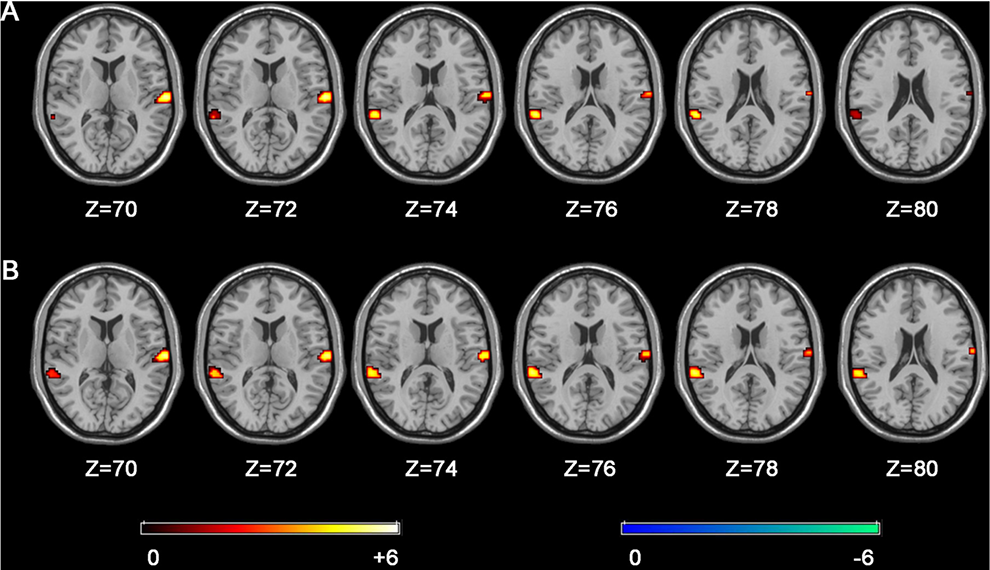

The Neural Asymmetry Deviations between Guitarists and Pianists

Ruijie Xu, Junchen Zhou, Siqi Liu, Shengyi Wang, Xiaolong Guo, and Jing Lu